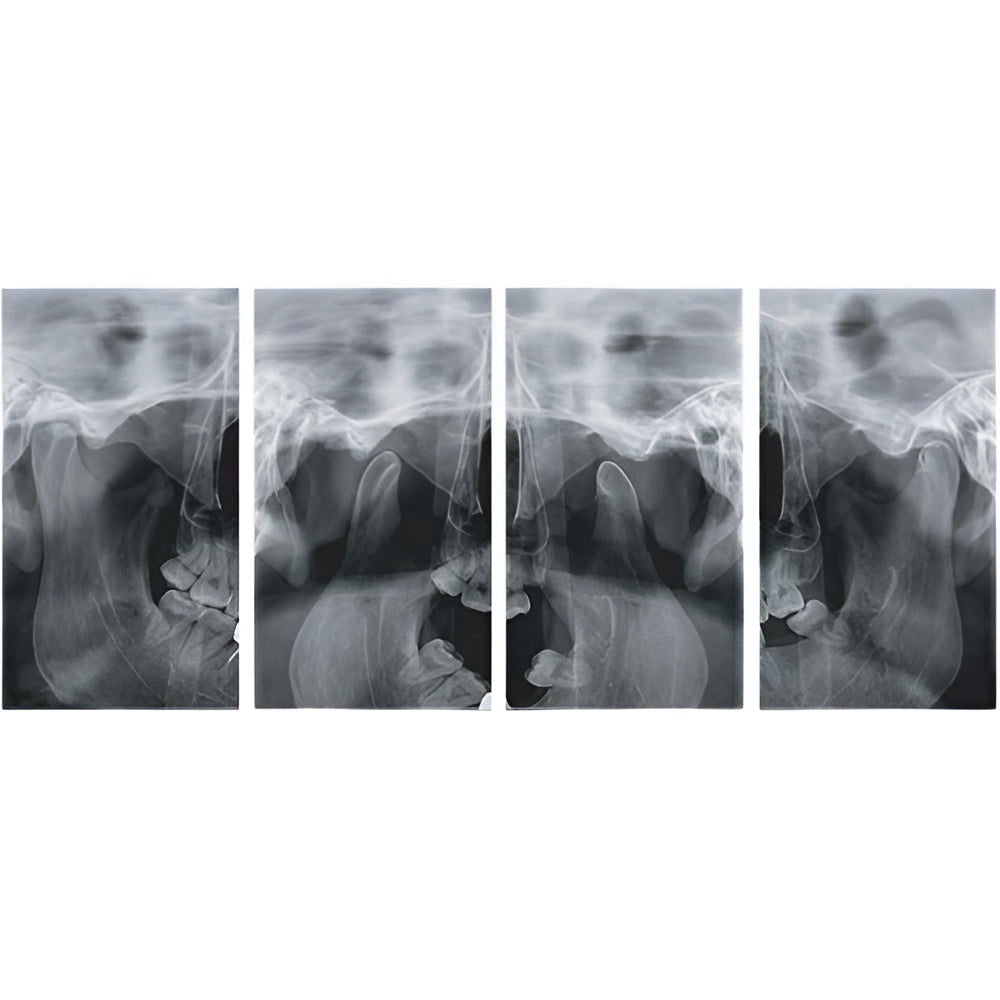

Genoray Papaya Plus Pan + CBCT (14x14 FOV)

Genoray Papaya Plus Pan + CBCT (14x14 FOV)

Papaya uses the CdTe sensor, which improves image quality while keeping radiation exposure to a minimum. The CdTe (Cadimium telluride) sensor overcomes the limitations of a CMOS sensor to always produce high quality images.

- Panoramic